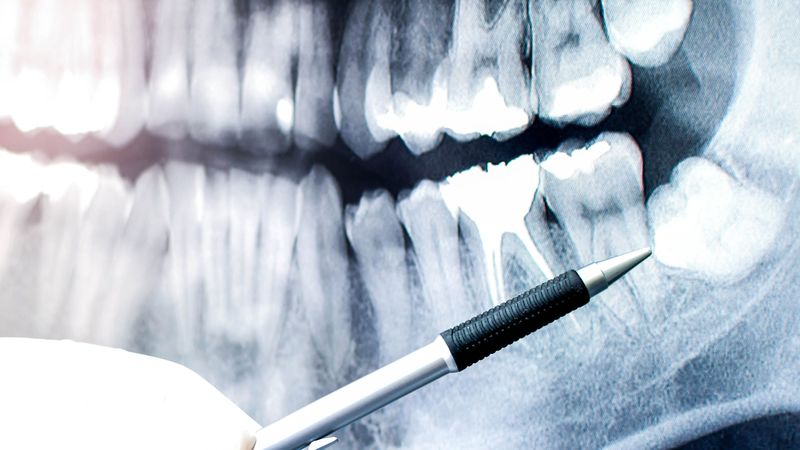

まず、親知らずが位置する場所は歯ブラシが届きにくいため、磨き残しが増え、口臭の原因となったり、気づかないうちに虫歯が進行したりするリスクがあります。その影響で周りの健康な歯も虫歯になる危険性が高まります。

次に、前回解説した歯周病の進行にも注意が必要です。歯肉の腫れや出血に気づかない場合でも、徐々に歯と歯肉の境目から菌が入り込み、顎の骨を溶かしてしまうことがあります。これが進むと健康な歯も抜けやすくなってしまいます。

さらに、親知らずの生え方によっては顎骨に圧力がかかり、変形したり歯並びが悪化する事もあります。顎関節症の可能性も高まるため注意が必要です。